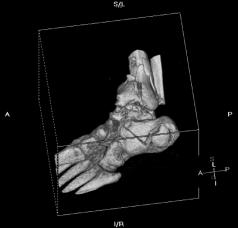

X-Rays and scans of the damaged right & left legs plus the pelvis

These x-rays were taken just after the accident. Some of the bones on the right leg have already been pushed back into the leg. The CT

scans show various views of the ankles and pelvis prior to any corrective surgery. Fibula bracing is clear in some of the images as well as

bracing that was used to secure the "open book" pelvis. In some of the last images it is apparent that the upper part of Liam’s left fibula is

broken. Liam was told that the pain he felt was most likely a muscle cramp. Nothing was done to repair this break and you will see in further

x-rays that the bone shifted and later fused in such a way as to add to the reduction of Liam’s leg length. The last photo shows the stint

used to block any potential blood clots from moving up.